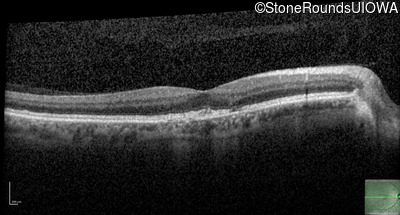

Optical Coherence Tomography - Right - 20/20

Exemplar / OCT Stack